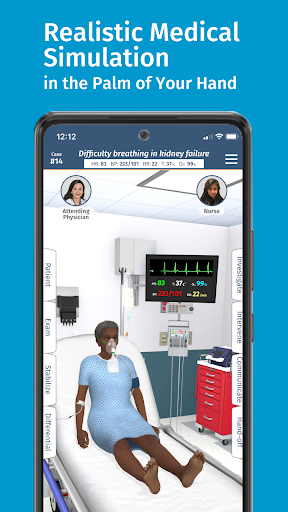

• Hơn 20 hình đại diện thực tế, bao gồm bệnh nhi và người lớn

Đào tạo mô phỏng theo yêu cầu của Full Code với các bệnh nhân ảo thực tế cho phép bạn thực hành các trường hợp phức tạp và nâng cao kỹ năng của mình bất cứ khi nào bạn có thời gian nghỉ ngơi, bất kể bạn ở đâu, trên các thiết bị bạn đã sở hữu. CẢI THIỆN SỰ TỰ TIN

Bệnh nhân và cảnh của chúng tôi trông và âm thanh chân thực hơn bao giờ hết.